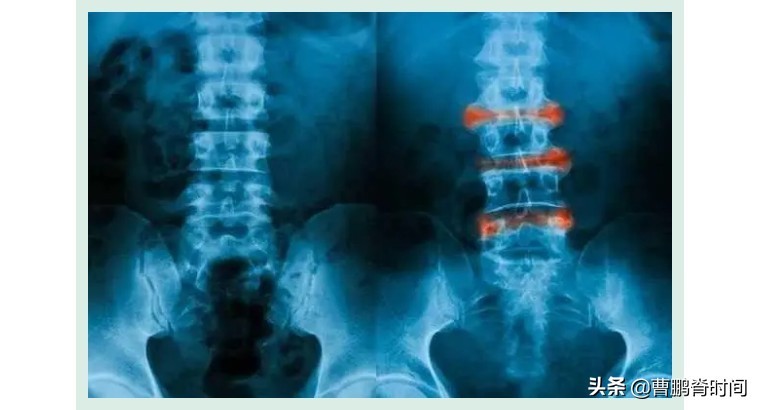

所谓强直,就是在炎症因子的作用下,脊柱的各个节段慢慢被融合,形成一种类似于竹节似的改变。

这种病在我们国家并不少见,大概200个人里边就有一个“强直”患者,尤其是40岁以下的年轻人最容易得此病。